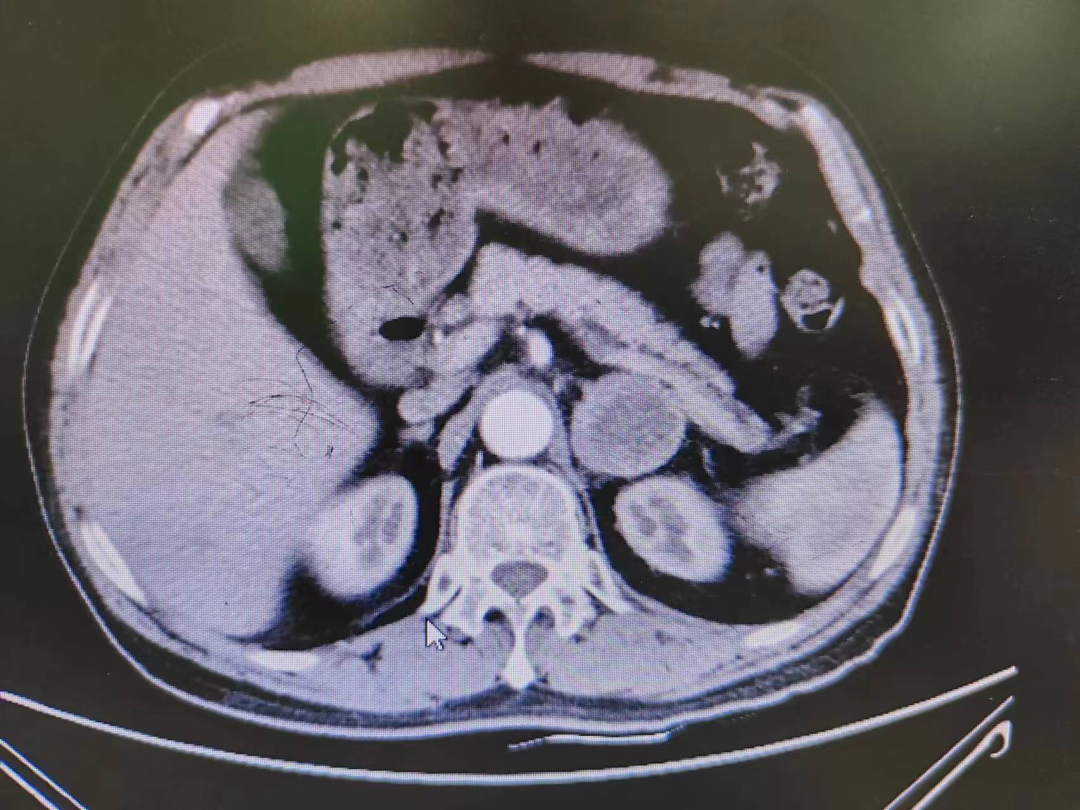

患者熊XX,,,,,,67岁,,,,,,因发明头晕、头痛曾多次于外院就诊,,,,,,到新桥医院就诊完善肾上腺CT思量嗜铬细胞瘤,,,,,,既往有高血压病史3年,,,,,,血压更高达230/120mmHg。。。。。。。我院高新区院区开诊后,,,,,,患者慕名而来。。。。。。。术前起劲完善血尿儿茶酚胺代谢产品(MNS)均显着升高,,,,,,患者于我院高新区院区及江南院区泌尿外科起劲控制血压、心率、血糖,,,,,,术前充分扩容。。。。。。。

因肿瘤位置位于肾蒂周围,,,,,,术中触碰肿瘤导致血压显着升高,,,,,,血压波动较大,,,,,,肿瘤外貌血供富厚,,,,,,不但需要手术医生富厚的临床履历和高明的手艺水平,,,,,,也是对医生心理素质、勇气和毅力的严肃磨练。。。。。。。

经由泌尿外科医师全体讨论,,,,,,在举行术前准备2-3周后,,,,,,再次请多学科讨论评估手术危害,,,,,,并与患者及眷属充分相同后于6月30日行腹腔镜下左侧肾上腺嗜铬细胞瘤切除术。。。。。。。手术在陈勇主任医师的指导下,,,,,,由孙伟副主任医师主刀及王传麟医师完成,,,,,,术中见肿瘤与肾蒂血管周围粘连细密,,,,,,与肾动脉、肾静脉分界不清,,,,,,稍有失慎,,,,,,可能损伤肾蒂血管可能需要行肾切除术,,,,,,且疏散肿瘤历程中血压波动较大。。。。。。。但在孙伟精准操作及疏散下,,,,,,与麻醉医生和手术护士团队亲近配合,,,,,,经由2小时的手术,,,,,,顺遂切除嗜铬细胞瘤,,,,,,并;;;;;ず蒙鲈嘌芗爸芪ё橹。。。。。。。术后患者顺遂出院,,,,,,术后血压及血糖控制优异。。。。。。。